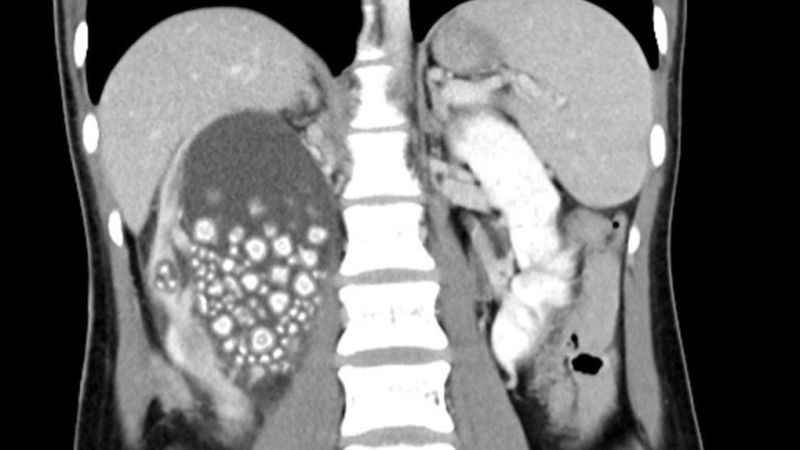

Tayvan’ın güneyinde yer alan Tainan şehrinde 20 yaşındaki Xiao Yu sırt ağrısı şikayetiyle hastaneye başvurdu. Yapılan tetkiklerin sonucunda böbreklerinde çok sayıda böbrek taşı tespit edilen Yu acil ameliyata alındı. Başarılı geçen ameliyatın ardından Yu’nun böbreklerinden 0.5-2 cm boyutlarında 300’den fazla böbrek taşı çıkarıldı.